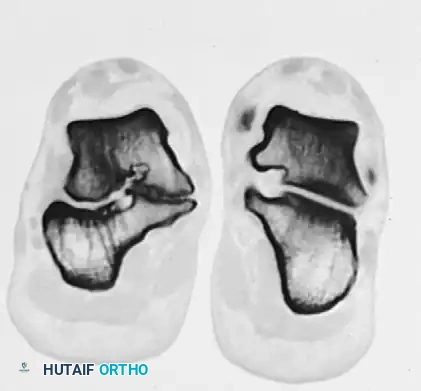

Advanced imaging is mandatory for surgical planning. While standard weight-bearing radiographs may demonstrate secondary signs such as talar beaking or the "C-sign" (a continuous C-shaped line formed by the medial outline of the talar dome and the inferior outline of the sustentaculum tali), Computed Tomography (CT) is the gold standard for defining the exact size, location, and osseous nature of the coalition.

FIGURE 82-84 C: Harris axial calcaneal view, traditionally used to visualize the middle and posterior facets, demonstrating an abnormal medial joint space.

FIGURE 82-84 D: Coronal CT scan confirming degenerative changes in the middle and posterior facets. Note the adaptive changes of the entire shape of the calcaneus and the bridging bone at the sustentaculum tali.